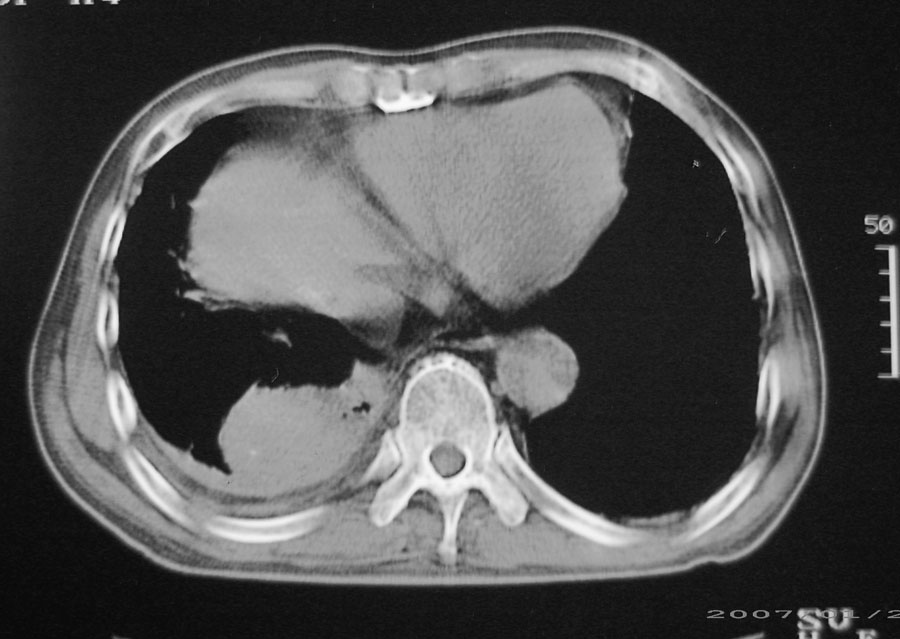

以下是引用hhcckk在2007-1-24 18:11:00的发言:[br]病灶周围胸膜反应比较明显,考虑炎症可能性大点,病人年龄较大,病灶成块状,肿瘤也不能排除,可可西里老师看片子的确很仔细,隔离肺暂时我觉得证据的说服力不大,上下层面显示条状影范围较长,可能是增厚的胸膜,可以做个增强鉴别一下

以下是引用天南地北在2007-1-24 18:00:00的发言:[br]1:右下肺内基底段类椭圆性肿快影:考虑1:右下球形肺炎2:右下肺隔离症,建议抗炎治疗后复查。[br]2:右肺及左下肺感染,右侧少量胸腔积液。